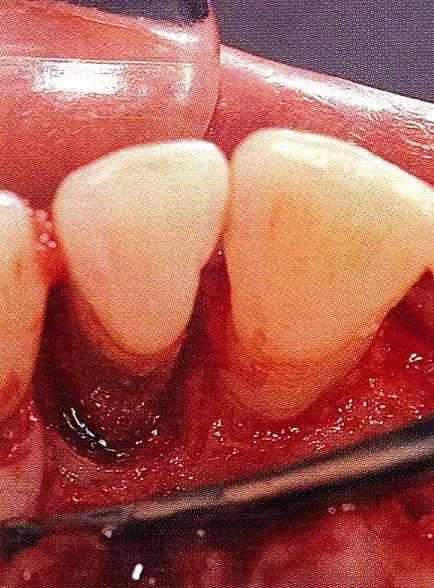

640.webp (4).jpg

▲圖7-5  此狀態(tài)下,左下5的遠(yuǎn)中存在牙槽骨不平整,因此進(jìn)行了骨修整。同時,將骨膜留存,進(jìn)行了齦瓣根尖側(cè)移動術(shù),去除了牙周袋。